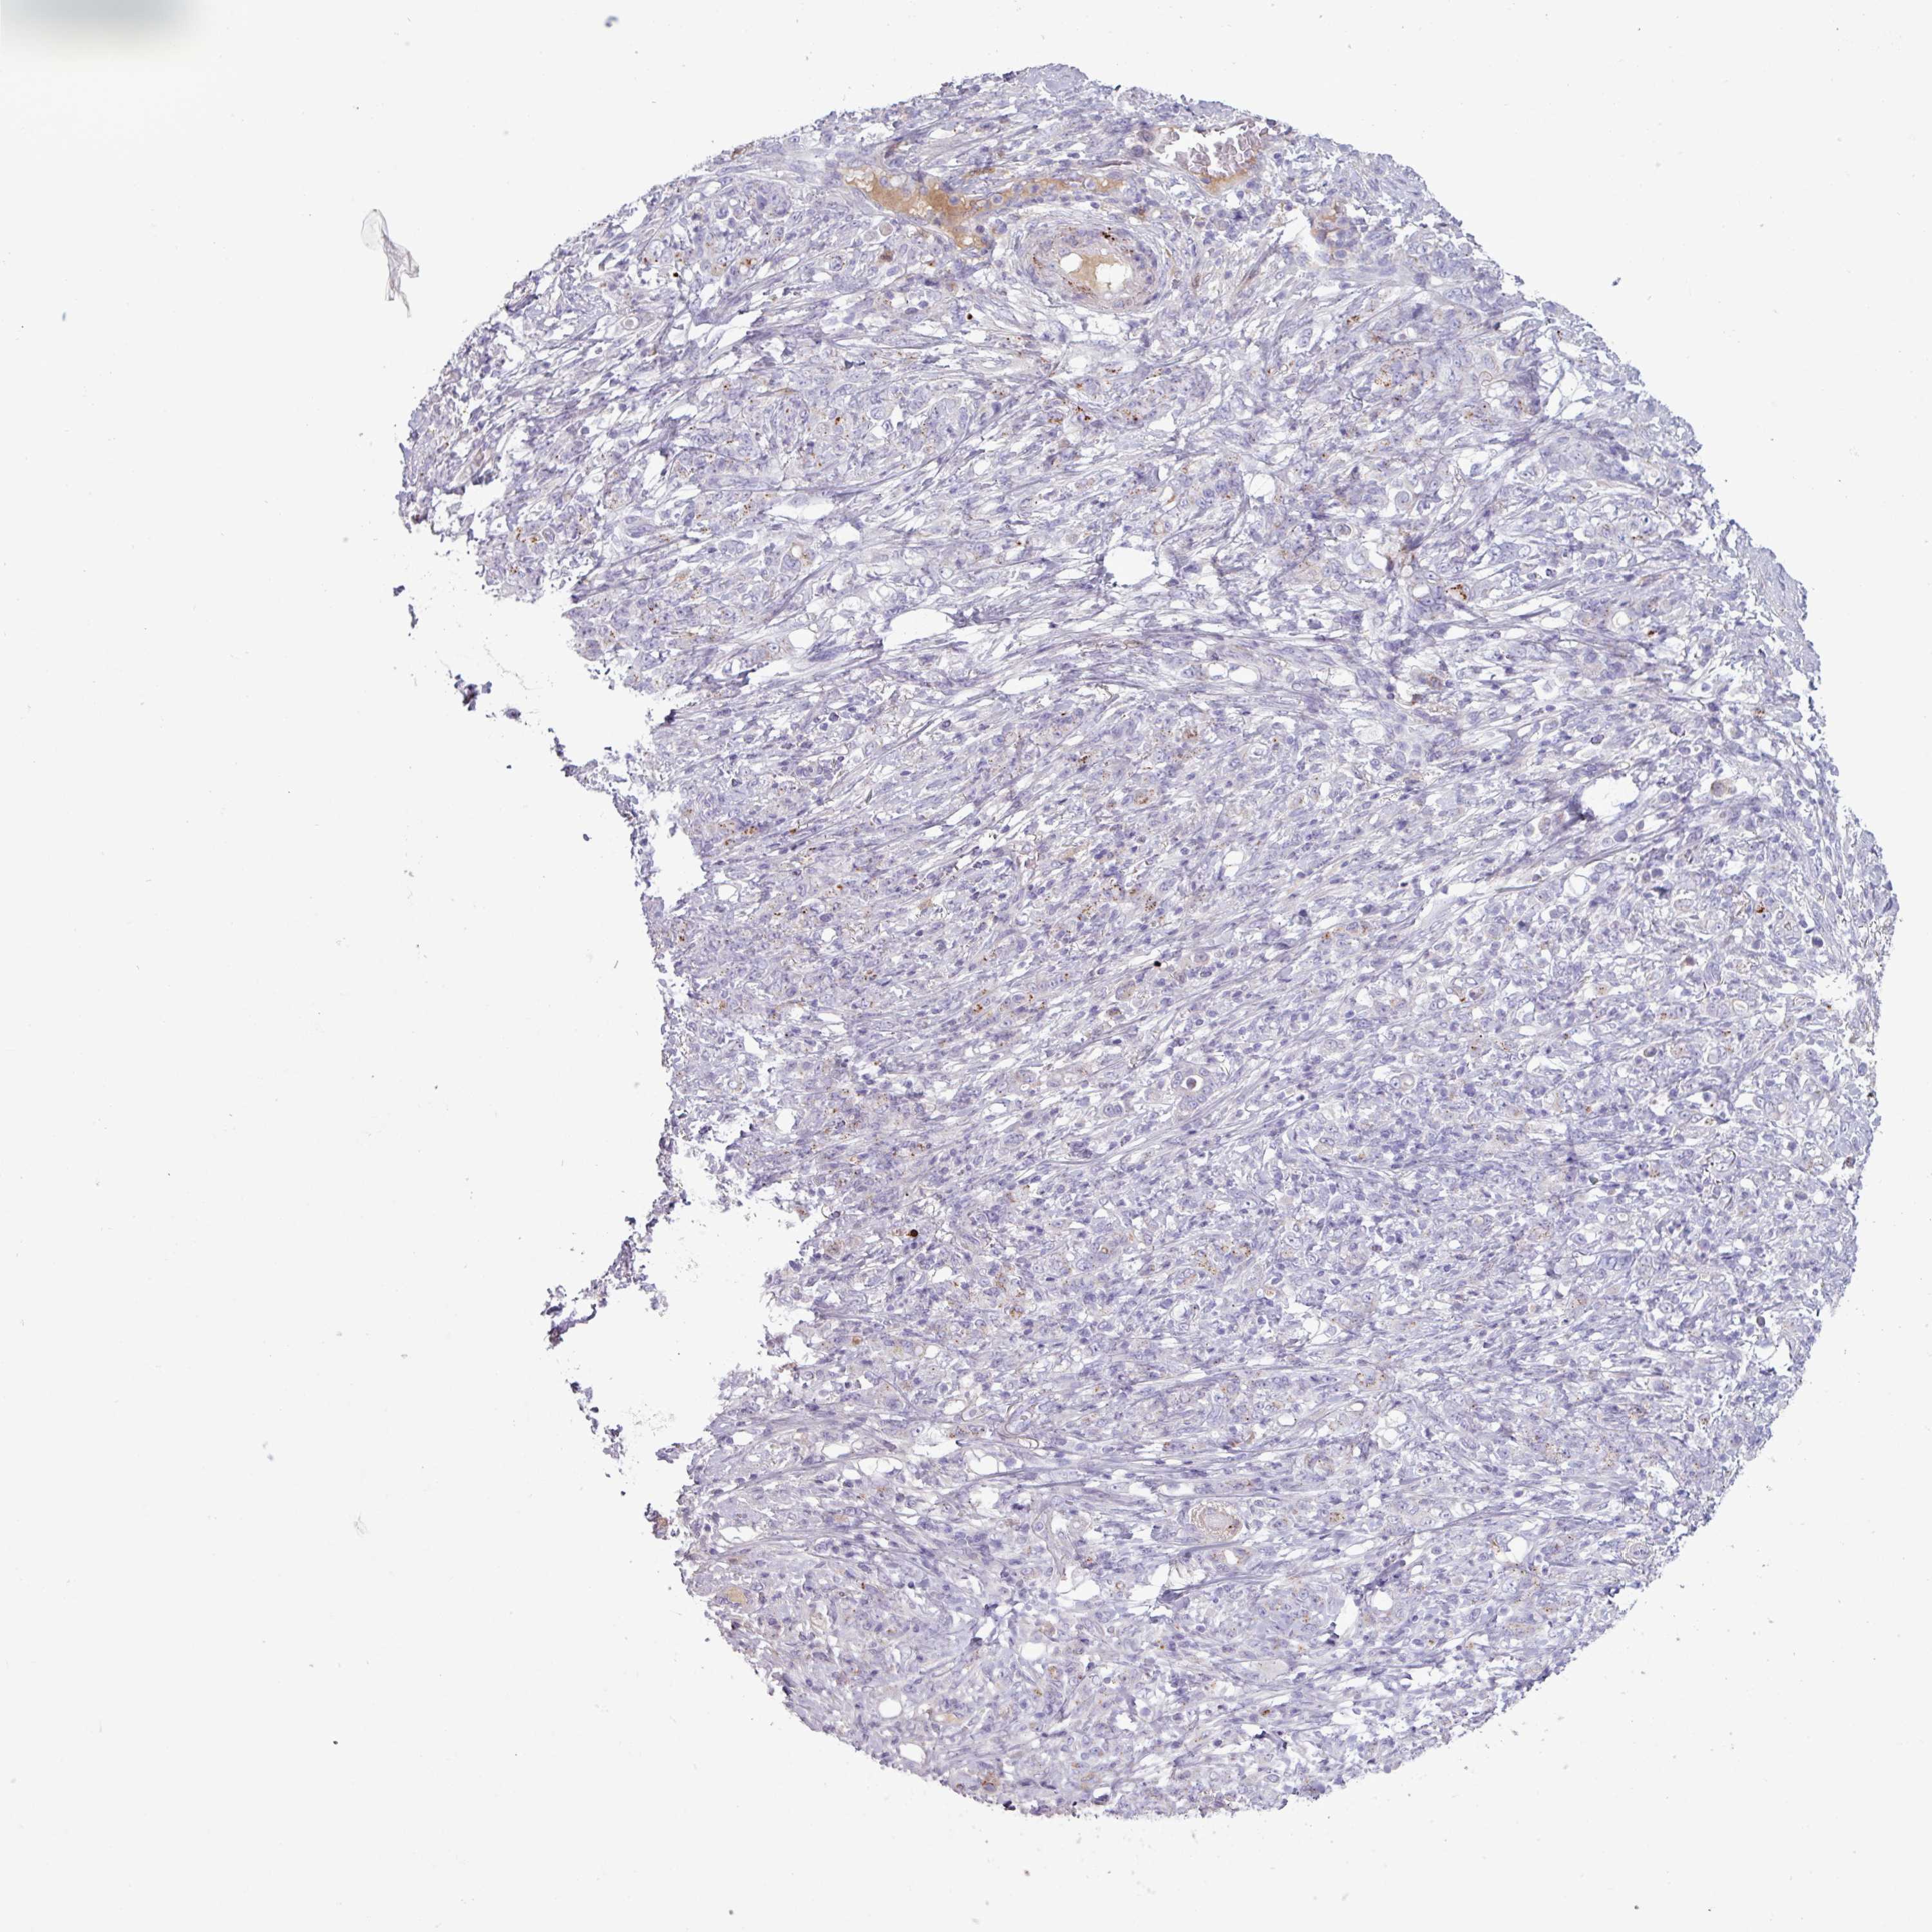

STOMACH CANCER - Protein expressioni

A mouse-over function shows sample information and annotation data. Click on an image to view it in a full screen mode. Samples can be filtered based on level of antibody staining by selecting one or several of the following categories: high, medium, low and not detected. The assay and annotation is described here.

Note that samples used for immunohistochemistry by the Human Protein Atlas do not correspond to samples in the TCGA dataset.

Antibody stainingi

Antibody staining in the annotated cell types in the current human tissue is reported as not detected, low, medium, or high, based on conventional immunohistochemistry profiling in selected tissues. This score is based on the combination of the staining intensity and fraction of stained cells.

Each image is clickable and will lead to virtual microscopy that enables deeper exploration of all samples and also displays staining intensity scores, fraction scores and subcellular localization as well as patient and tissue information for each sample.

HPA046356

Staining

Not detected

Negative

None

Adenocarcinoma, NOS